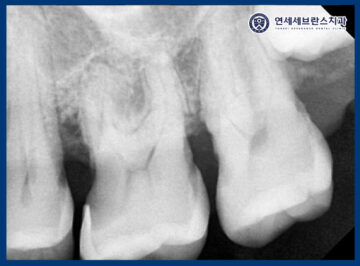

CT를 촬영하여 확인해 보았을 때,

뿌리 끝 염증이 이미 신경까지 퍼져있었으며

조금만 더 늦었으면 치아 염증이

아래턱, 얼굴 감각까지 영향을 미칠 수 있는 상황이었으며

당장 임플란트 보다는 염증 제거 및

발치 후 치유 양상 확인이 필요했습니다.